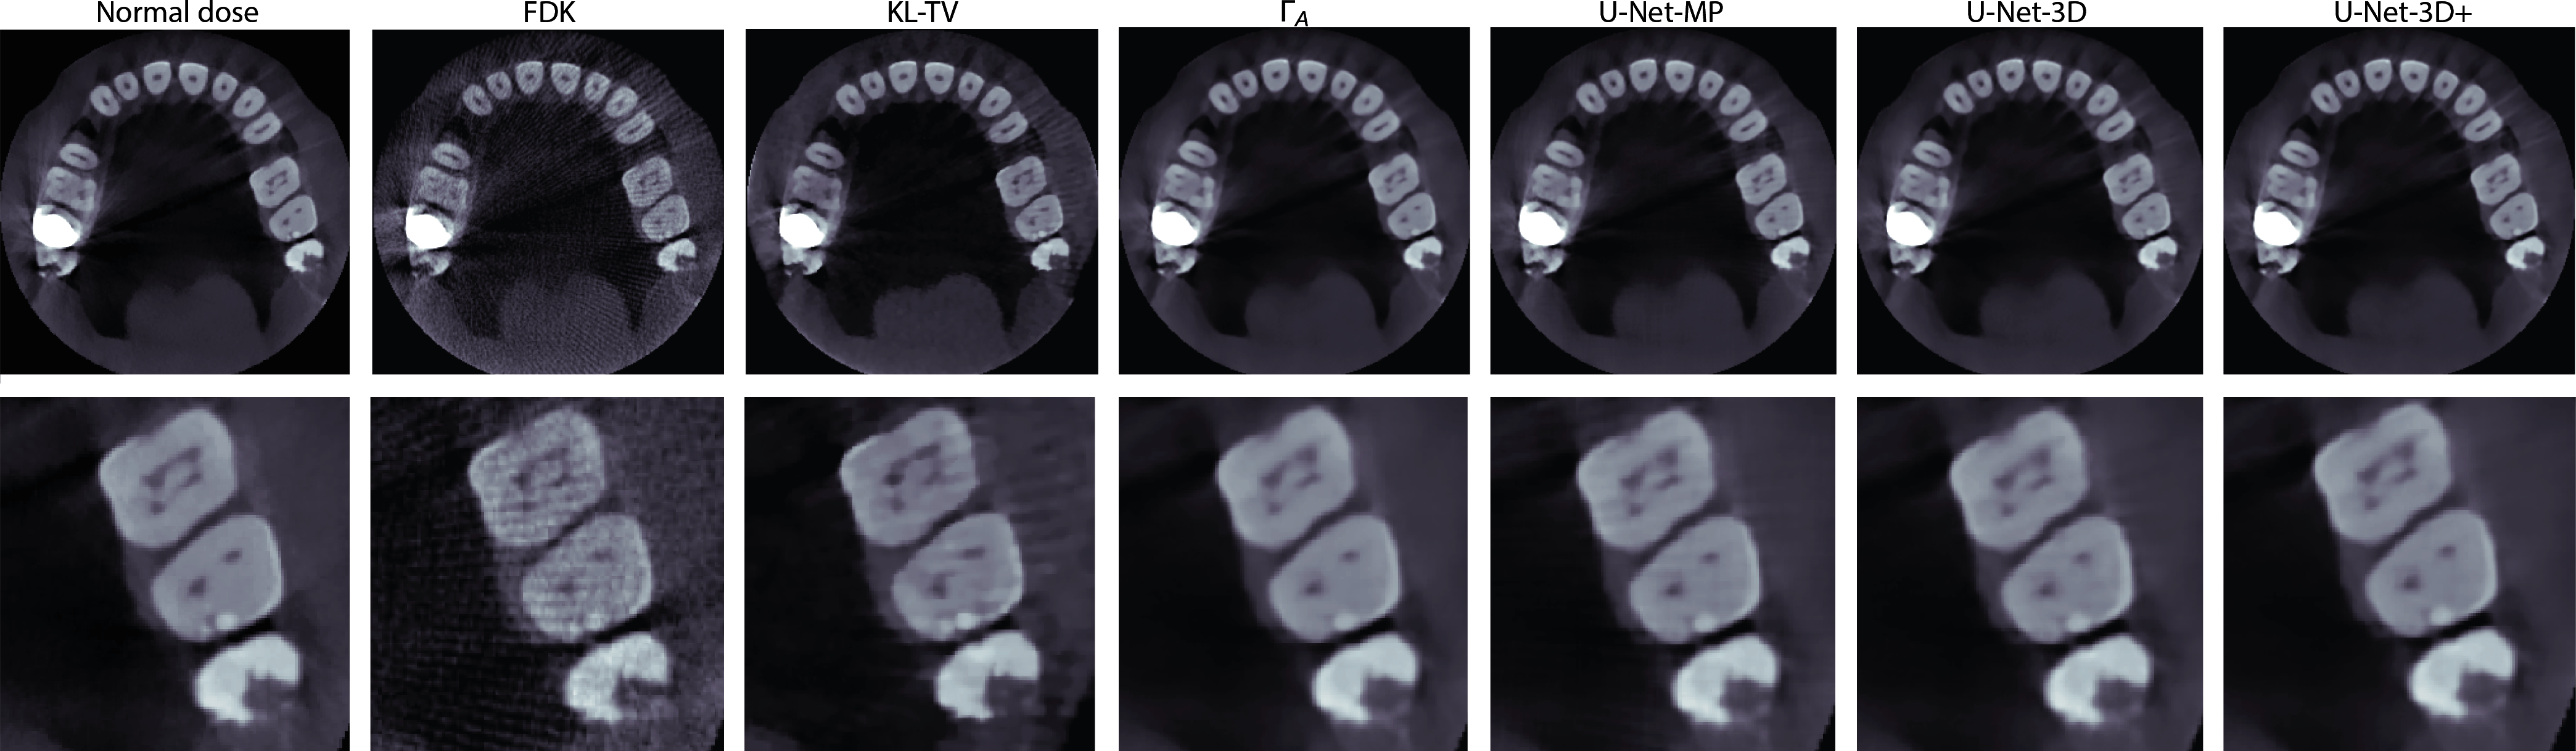

Figure 1 shows an axial slice in which a crown on the left maxillary second molar generates metal artifacts. These artifacts, which are much more prevalent when few projections are used, are particularly noticeable in FDK and KL-TV reconstructions, whereas the methods based on deep learning reduce them considerably. The canals of the left first molar are better resolved with U-Net than with the other methods.

The zoom at the center of each slice enables a better comparison of the volumes at the output of the networks. ΓAsubscriptΓ𝐴\Gamma_{A} and U-NET-3D+ offer the best images, with effective denoising while still correctly preserving structures. Object contours in the U-Net-3D output volume are slightly less sharp than those of the others. In the volume processed by the U-Net-MP, a grid pattern is visible in the lighter areas of the teeth, due to inhomogeneities in the volume output from ΓSsubscriptΓ𝑆\Gamma_{S}.

Refer to caption

Fig. 1: Example of axial slice containing metal, and a zoom of the left premolar and first molar for the different methods.